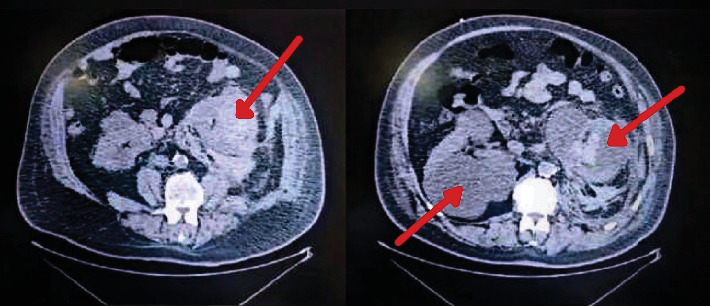

This case report presents a compelling instance of Wunderlich syndrome (WS), a rare and nontraumatic medical condition characterized by spontaneous renal hemorrhage into the subcapsular and perirenal spaces. WS poses unique diagnostic and management challenges due to its sudden and substantial hemorrhage presentation that is life-threatening, often accompanied by acute flank pain, hemodynamic instability, and the presence of a flank mass. While the exact pathogenesis remains debated, WS can arise from various renal pathologies, including neoplastic and nonneoplastic conditions. In this case, a 65-year-old male with a complex medical history, including polycystic kidney disease, presented to the emergency room with massive hematuria leading to an abrupt severe drop in hemoglobin levels and hemodynamic instability. Despite aggressive management, including transfusions, the patient ultimately underwent an urgent open left radical nephrectomy due to the severity of the condition and distorted anatomy. Additionally, the report draws attention to the potential use of tranexamic acid in WS cases, stressing the importance of balancing its benefits against associated risks. This case highlights the critical importance of recognizing and promptly addressing WS, highlighting the diverse etiology of this condition, the role of tranexamic acid in controlling bleeding, and the lifesaving role of nephrectomy in cases of significant bleeding and hemodynamic instability.